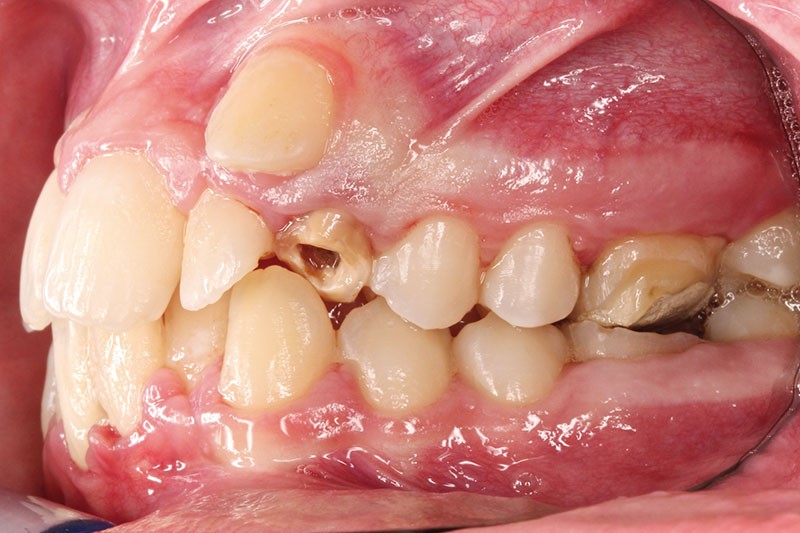

• Endo-buccal : Younesse présente un contrôle de plaque dentaire insuffisant, la persistance de 53 et 63, des soins en cours de réalisation sur 26 et 36, un encombrement maxillo-mandibulaire avec infravestibulotopie de 23 et une suspicion d’inclusion de 13 sur un schéma de Classe II subdivision droite (fig. 3 à 7).

L’examen parodontal révèle une gingivite généralisée ainsi qu’un parodonte très fin et une absence de profondeur vestibulaire.